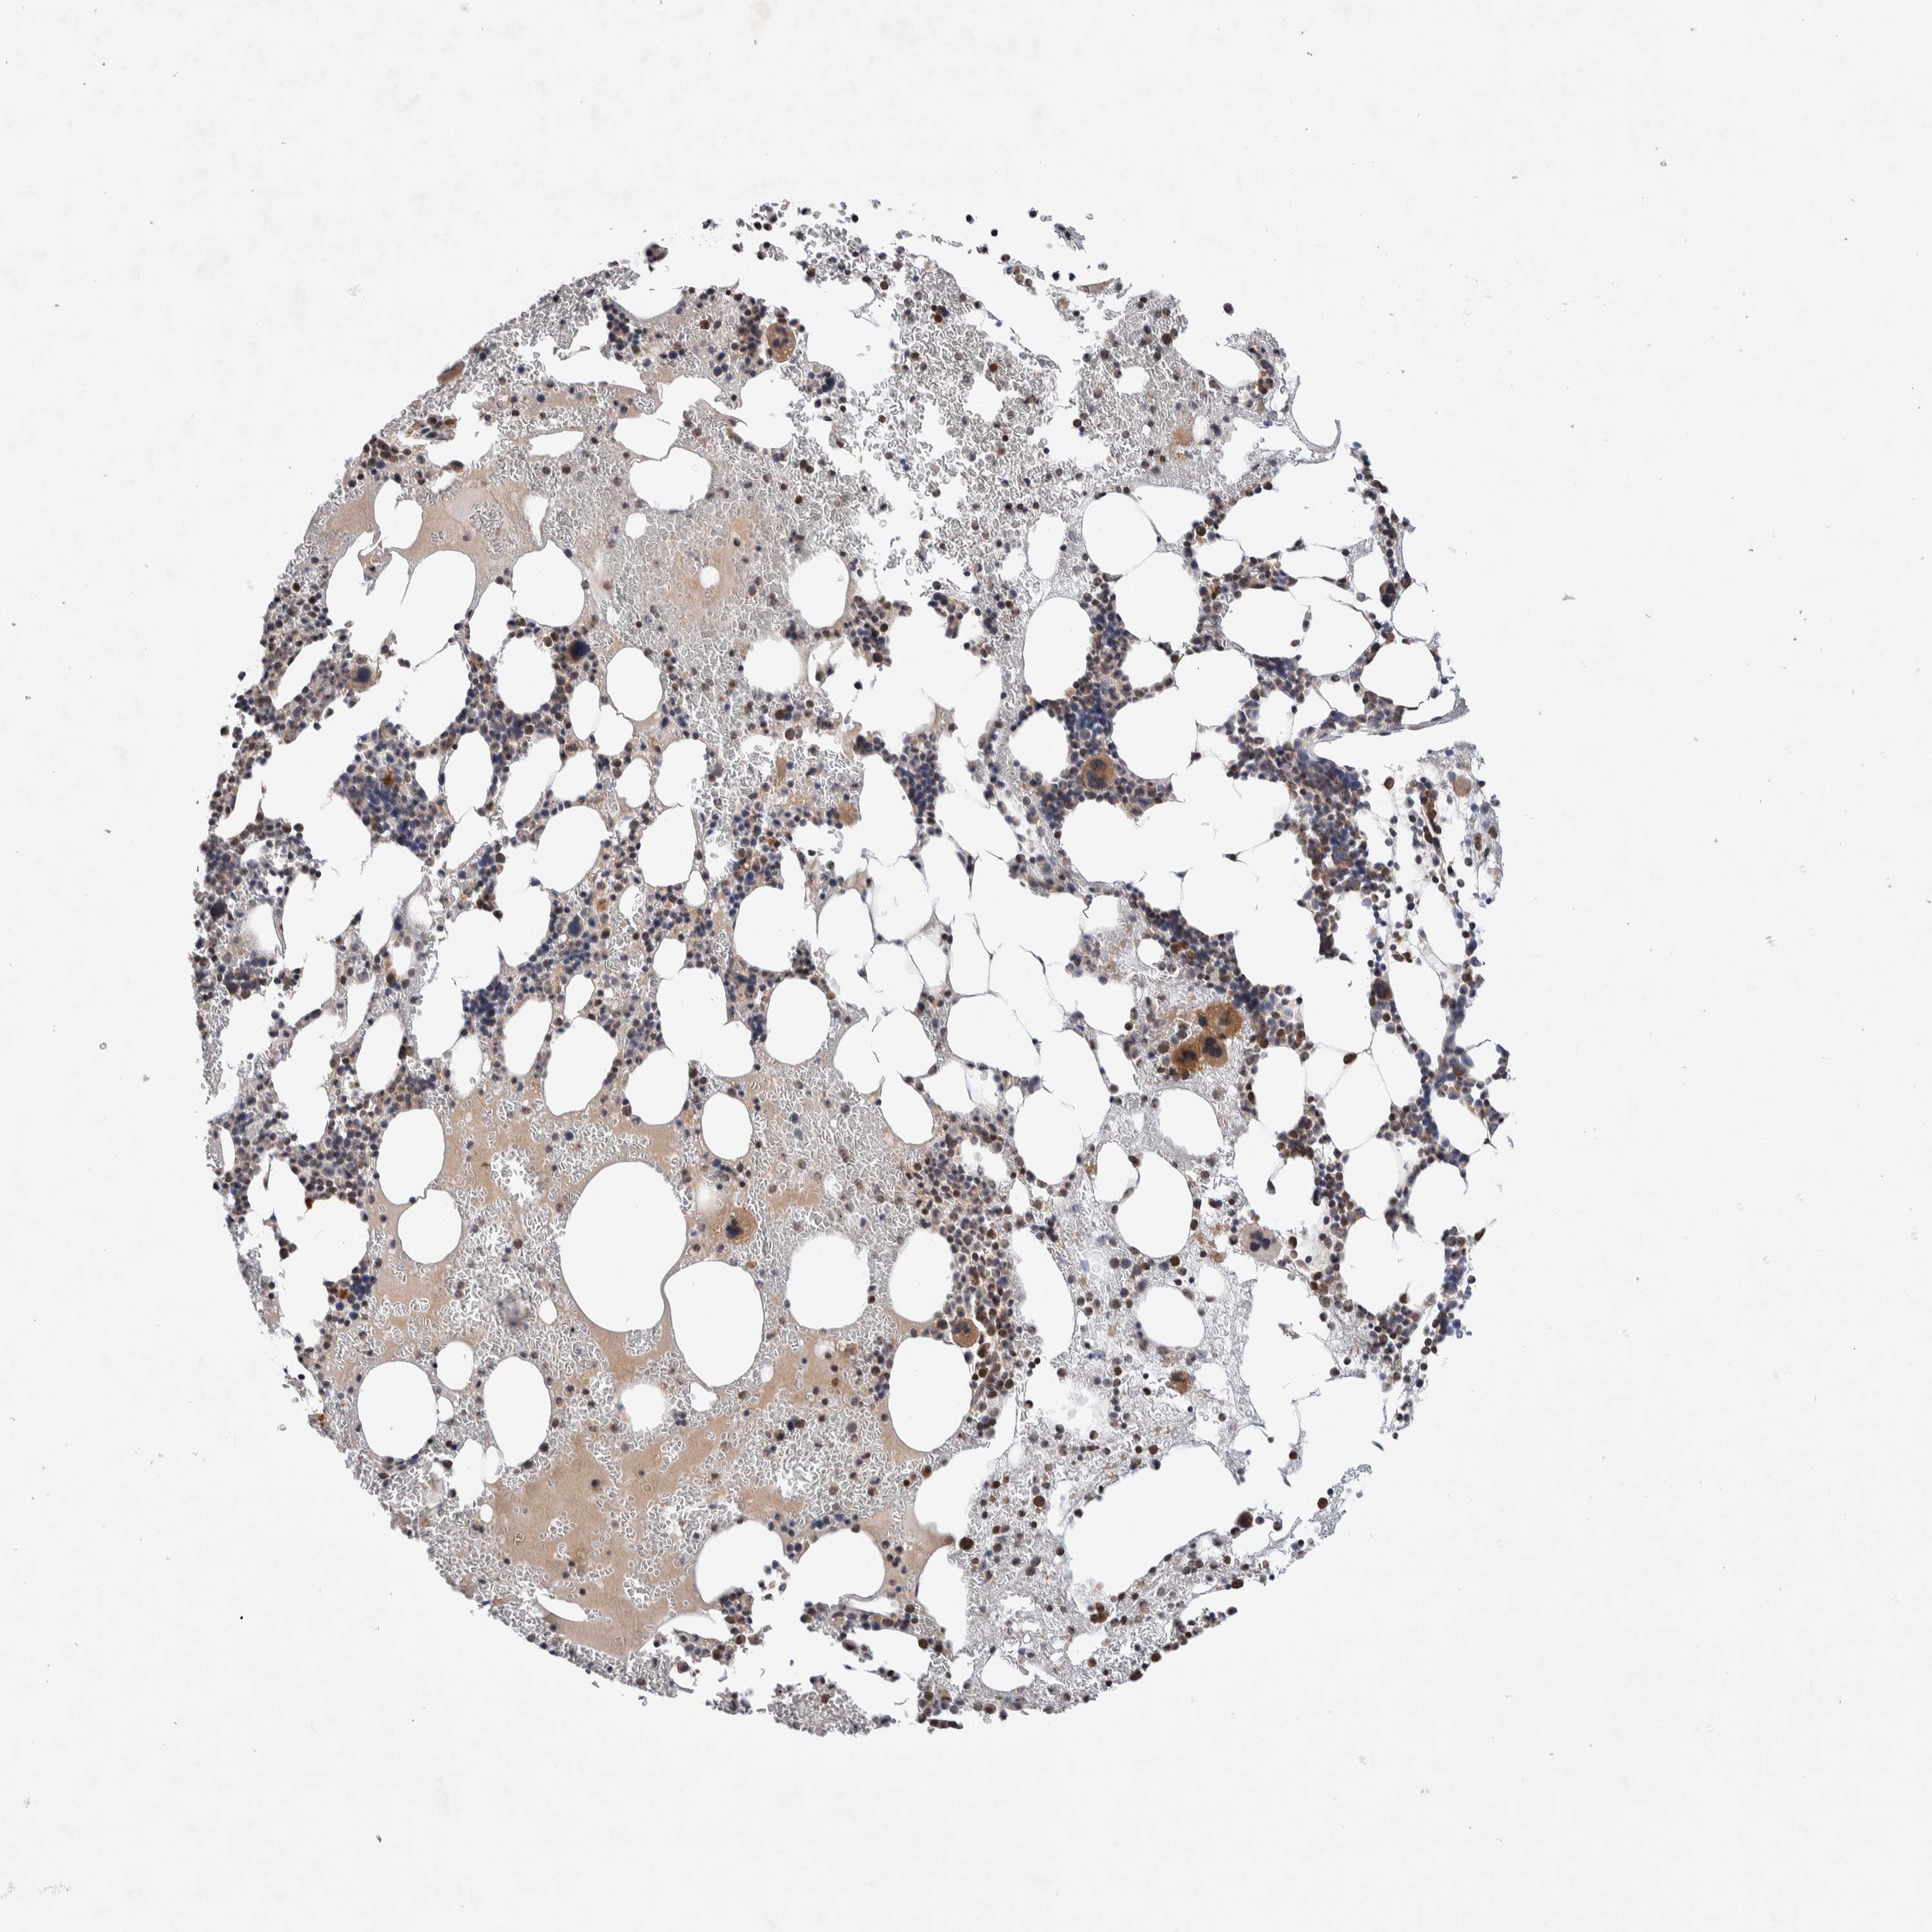

LZTS1